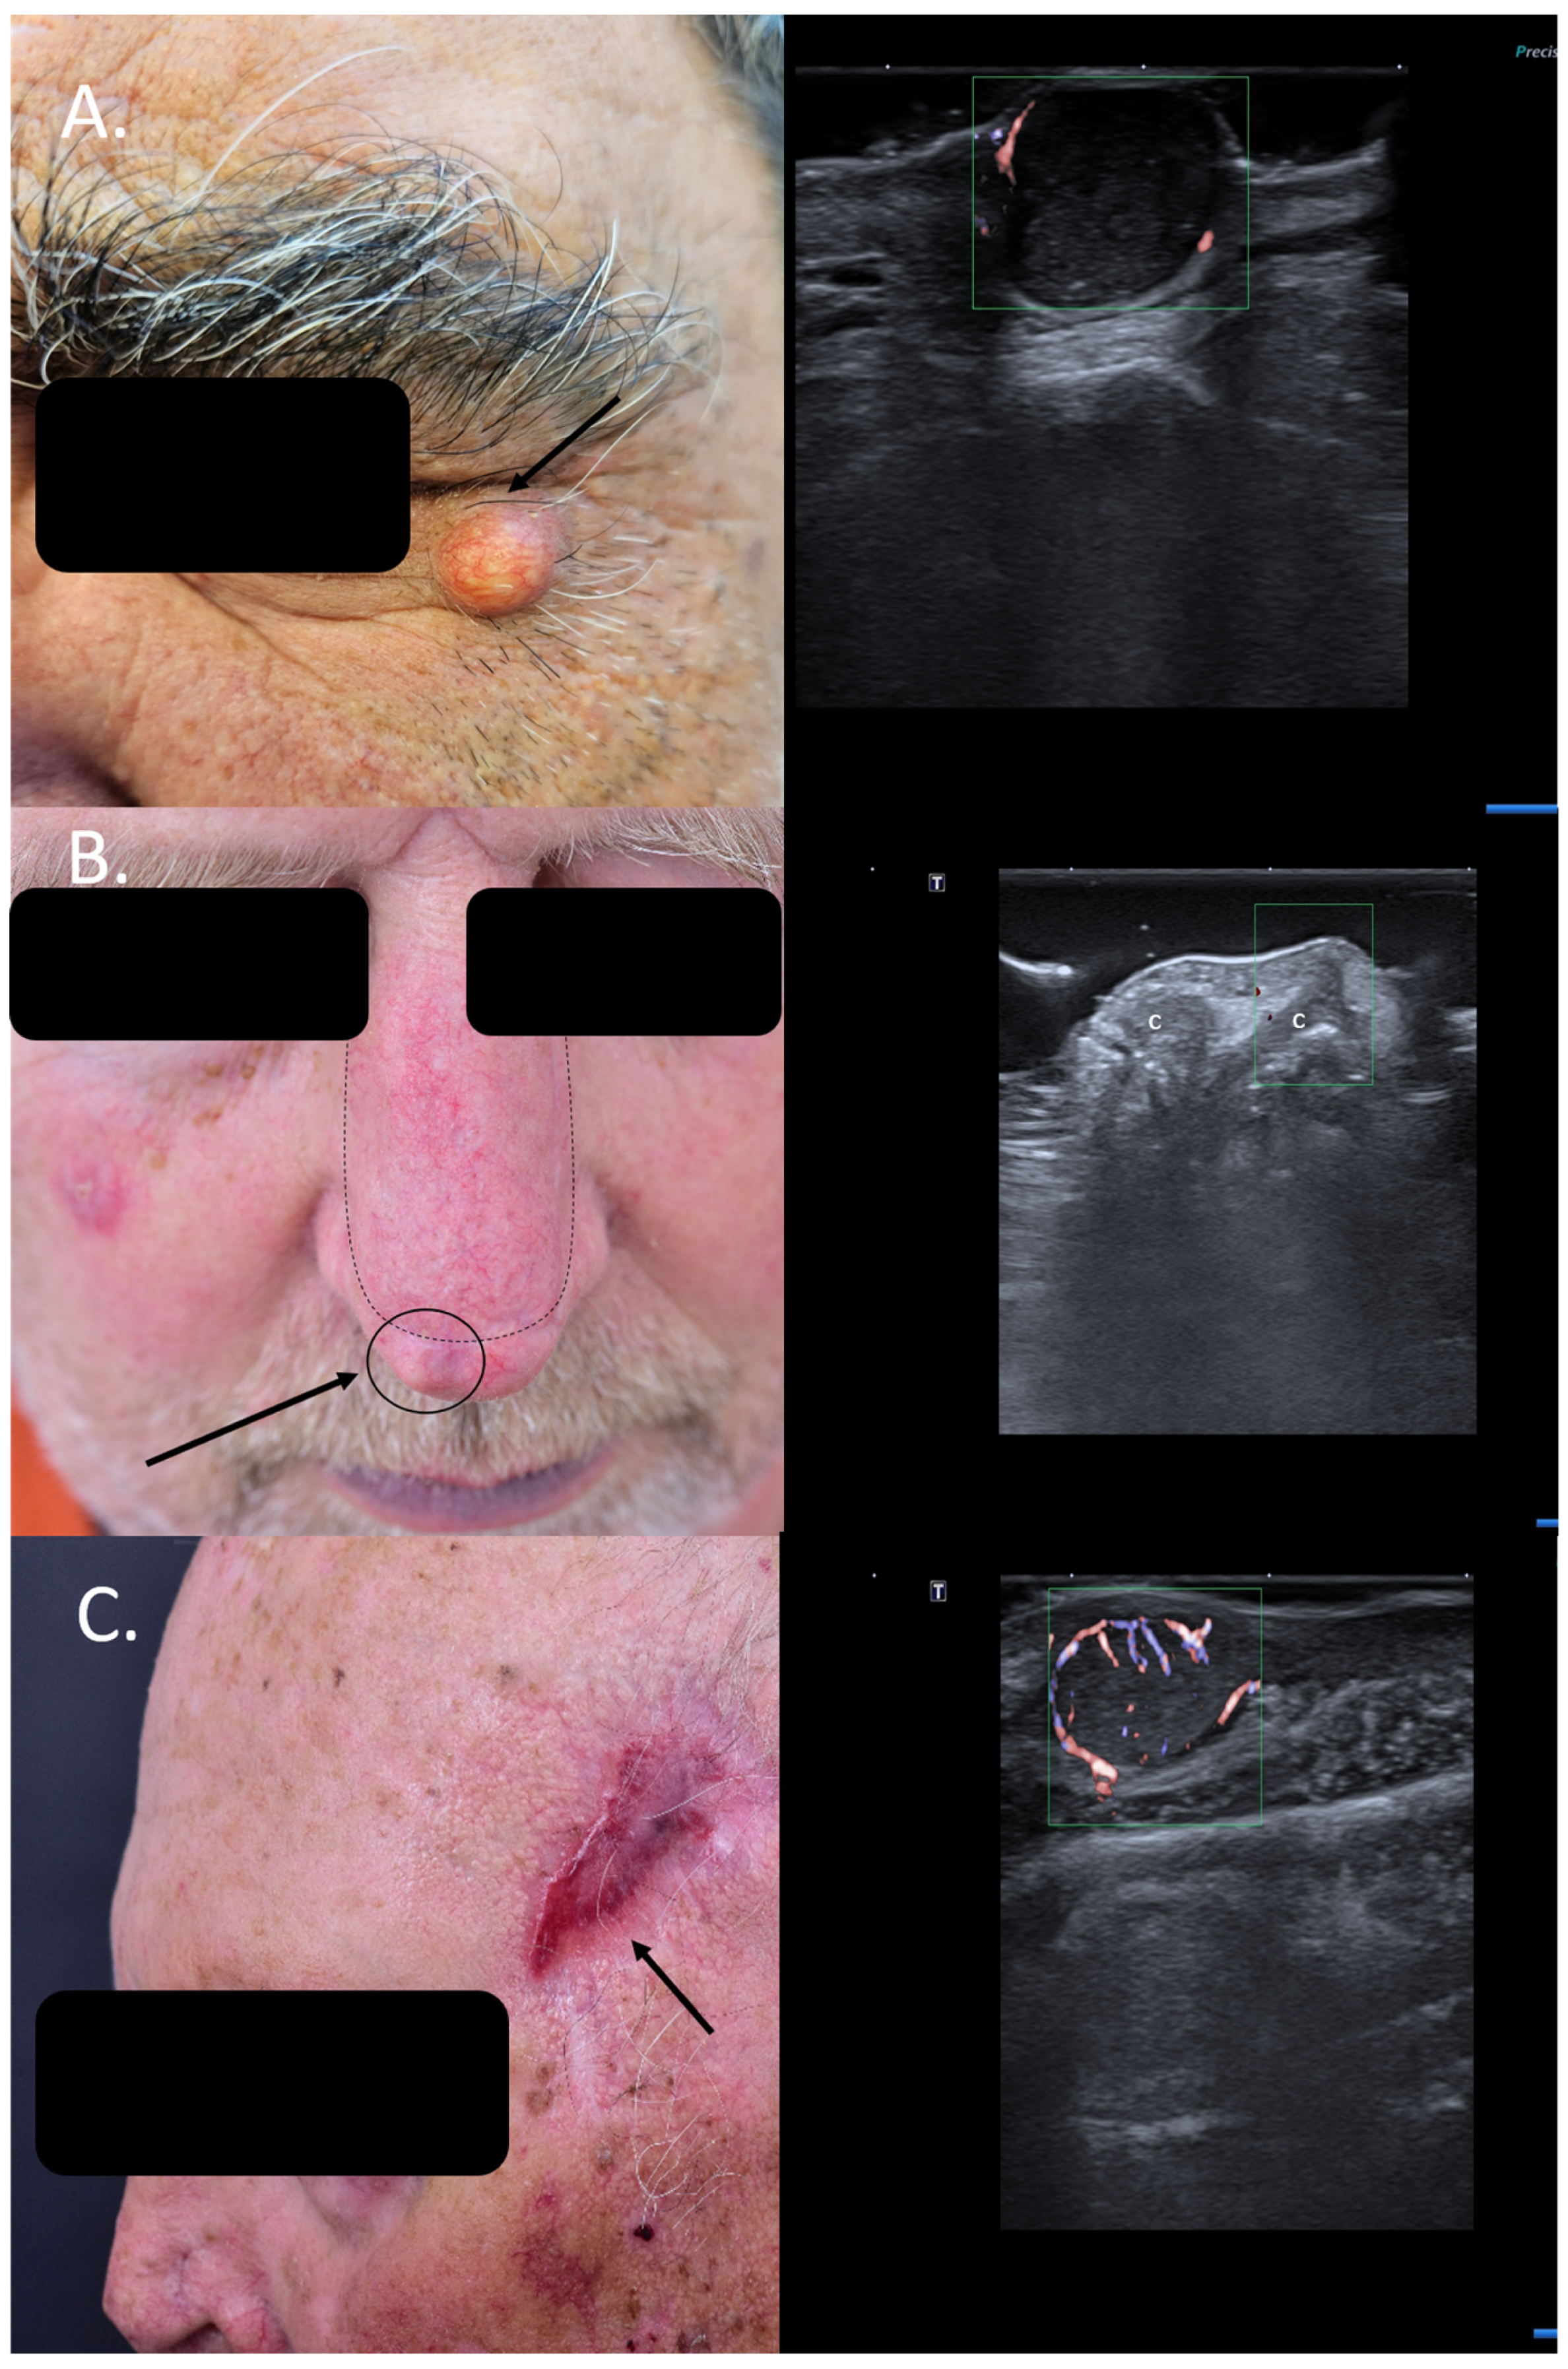

2. Enhancement of Diagnostic Accuracy, Avoidance of Misdiagnosis, Early Identification of Local Relapse

3. Lateral Margin Assessment

4. Assessment of the Tumor Infiltration Depth

7. Choice of Surgical Approach

8. Preoperative Neuro-Vascular Mapping